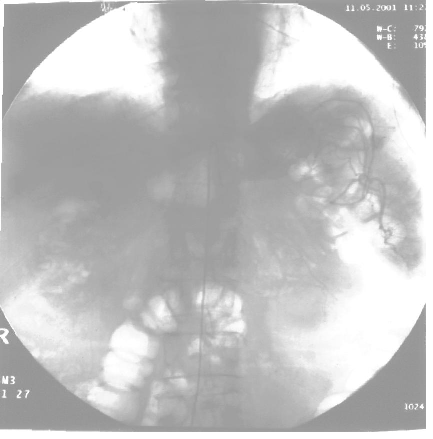

- Arteriografia selettiva del tripode celiaco -

Si ringrazia il dott. Carella per la gentile collaborazione alla stesura di questa pagina web che tratta di un'arteriografia selettiva dei vasi mesenterici  (arteria gastrica sx, tripode celiaco e mesenterica superiore) relativa ad un paziente che presentava melena e formazione riccamente vascolarizzata, già in precedenza evidenziata con indagine TAC addome dallo stesso radiologo. L'esame è stato eseguito presso la sezione angiografica dell' Ospedale Barone Romeo di Patti.

1) il catetere con cui viene immesso il mezzo di contrasto che viene inserito tramite l'a. femorale di destra, l'aorta addominale fino al tripode celiaco.

2) I rami pancreatico duodenali superiori forniscono modesto circolo ad una formazione già descritta, che vedete sulla sinistra dell'immagine (destra per il paz).

3) Si evidenzia, dunque, un circolo anomalo che è fornito dai rami pancreatico-duodenali inferiori (ramo della mesenterica superiore con intenso efflusso  parenchimografico e scarico venoso precoce. Molto bella l'immagine parenchimografica della lesione.

L'esame, dunque, conferma la presenza di una neoformazione riccamente vascolarizzata con scarico venoso precoce che viene irrorata dai rami dell'a. pancreatico-duodenale inf.(rami mesenterici e pancreatico duodenali superiori del tripode celiaco).